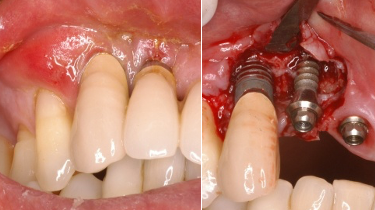

< インプラント周囲炎 >